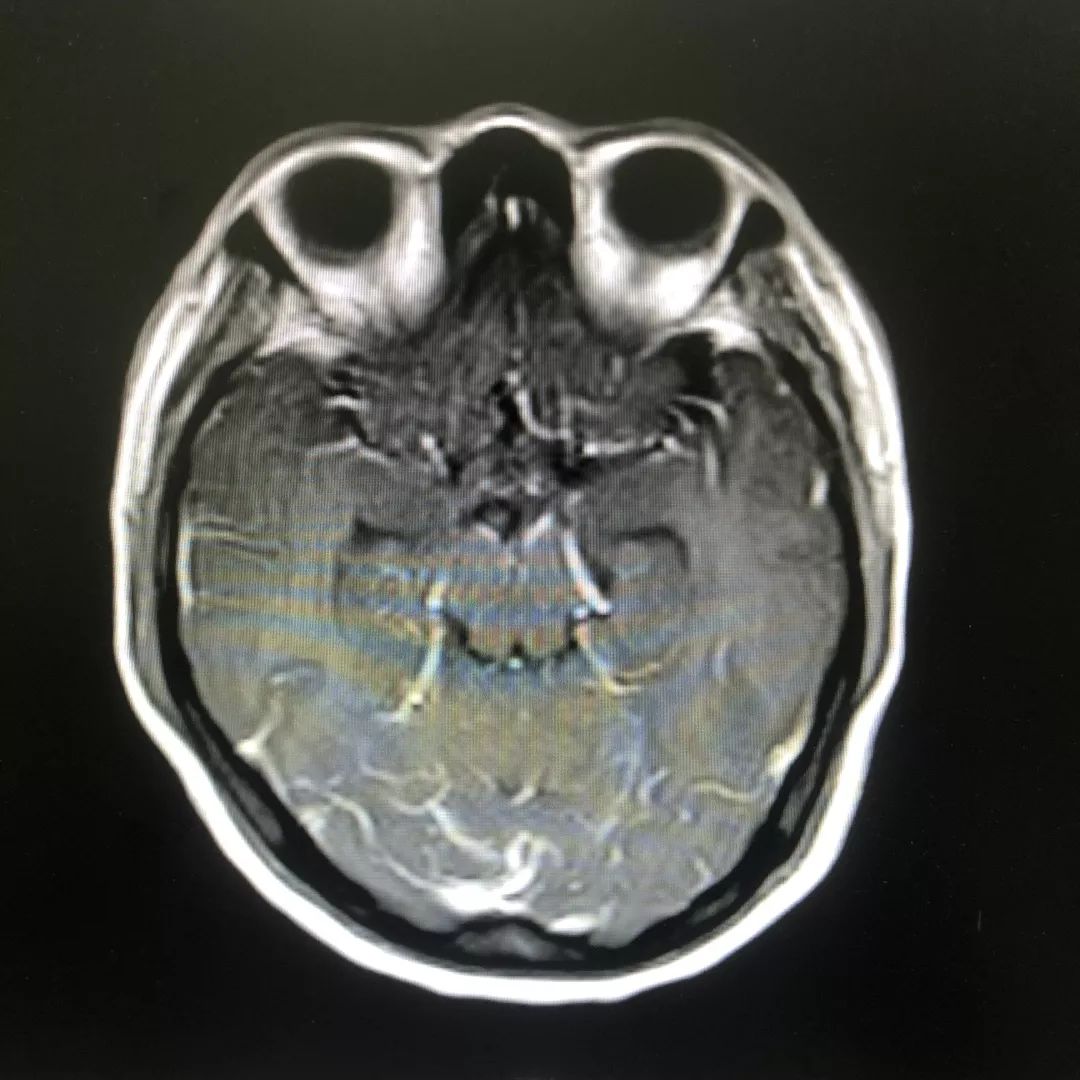

头颅增强磁共振:脑膜多发线样增强影